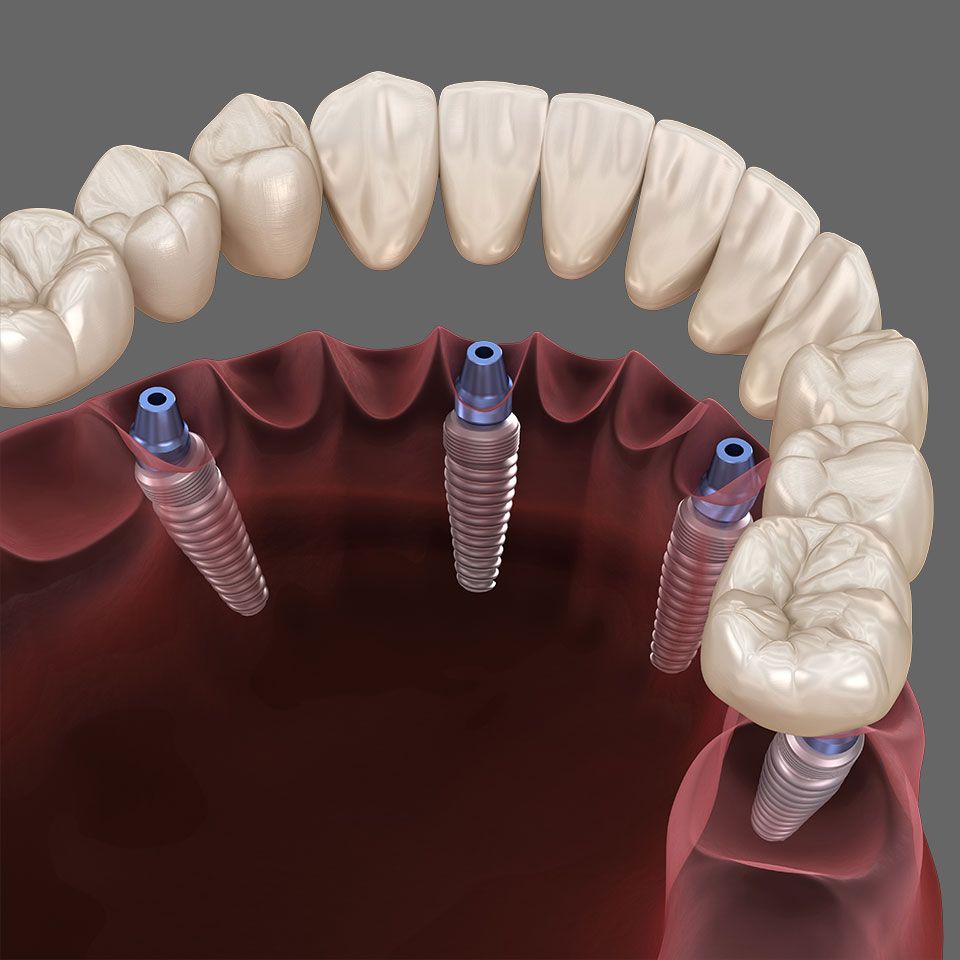

Die Alternative dazu ist festsitzende Zahnersatz auf Implantaten. Fast so gut wie ein natürlicher Zahn erfüllt ein auf Implantaten fixierter Zahnersatz die Aufgaben beim Zubeißen, Kauen, Sprechen und Lachen.

Diese künstlichen Zahnwurzeln sind zumeist aus Titan – einem gut verträglichen (biokompatiblen) Material. Sie werden in den Kieferknochen eingesetzt, wo sie mit dem Knochen fest verwachsen. So können sie einer Einzelkrone, Brücke oder Zahnprothese stabilen Halt verleihen.

Perfekter Tragekomfort und Sicherheit: Prothesenträger profitieren von den Vorteilen, die es nur bei Implantaten gibt

- sicheres Gefühl beim Essen, Trinken und Sprechen ohne die Gefahr, dass die Prothese „verrutscht“

- erheblich verbesserter Geschmackserfahrung bei gaumenfreier Gestaltung (keine Gaumenplatte).